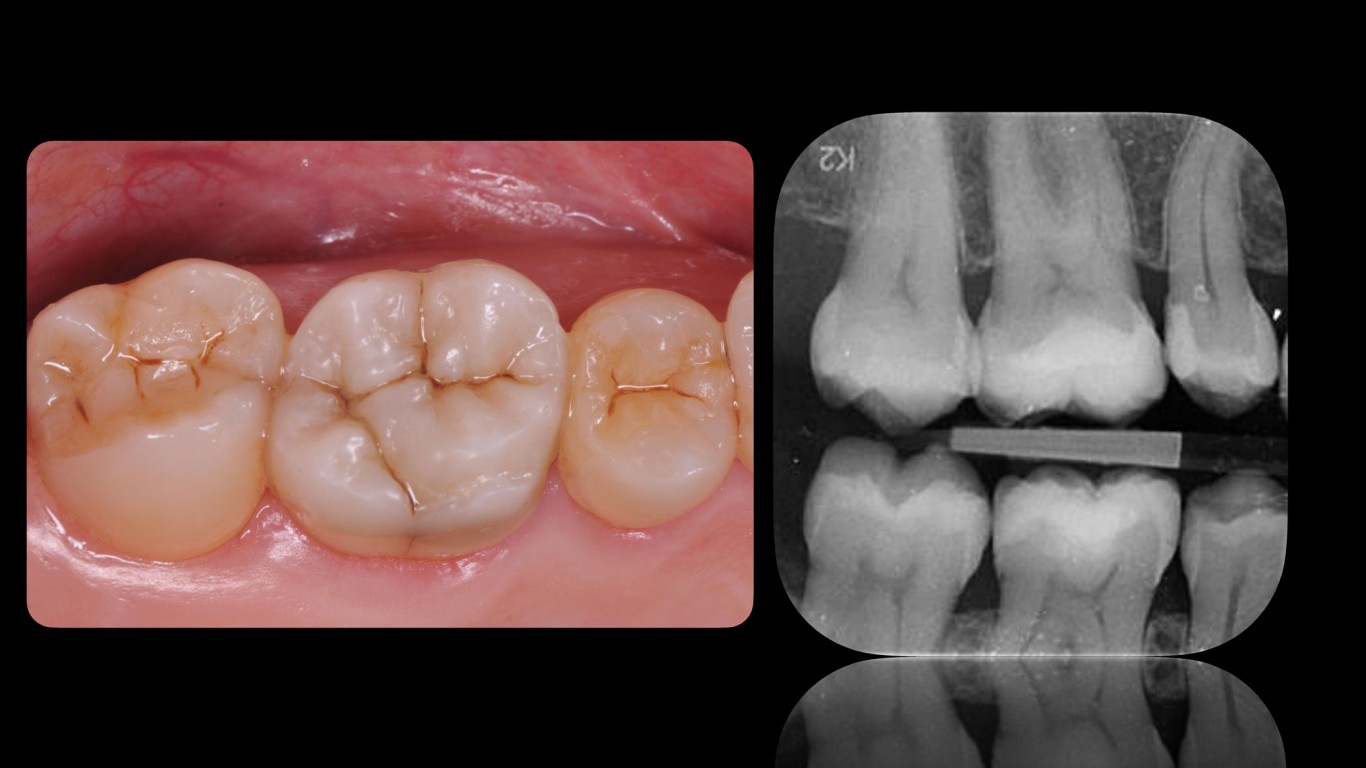

Slika 22. Finalni rezultat godinu dana nakon restaurativnog tretmana.

Slika 23. Radiografski snimci pre (A), nakon tretmana (B) i godinu dana nakon tretmana (C).